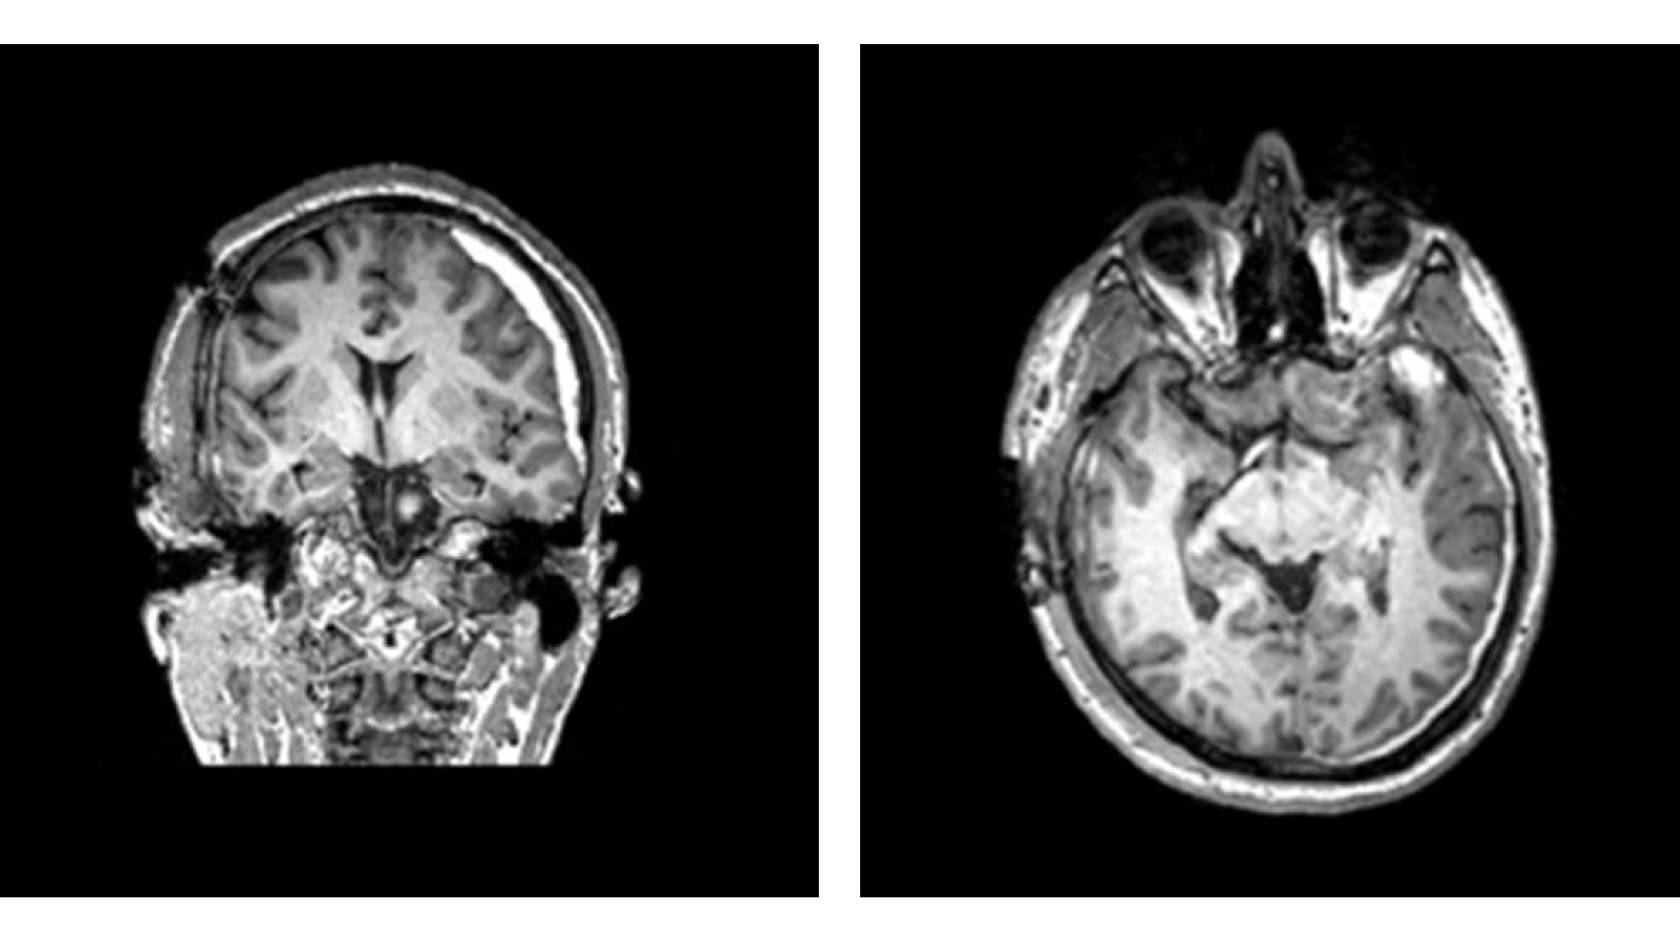

Another study that could help identify patients for the current trial showed that patients with certain patterns of injury that are visible on their CT scans were less likely to make a complete recovery a year later.

Trial participants must enroll on the day of their injury, so they can be treated promptly. They must have a CT scan showing evidence of bleeding, and a blood test and exam that indicate moderate to mild TBI.